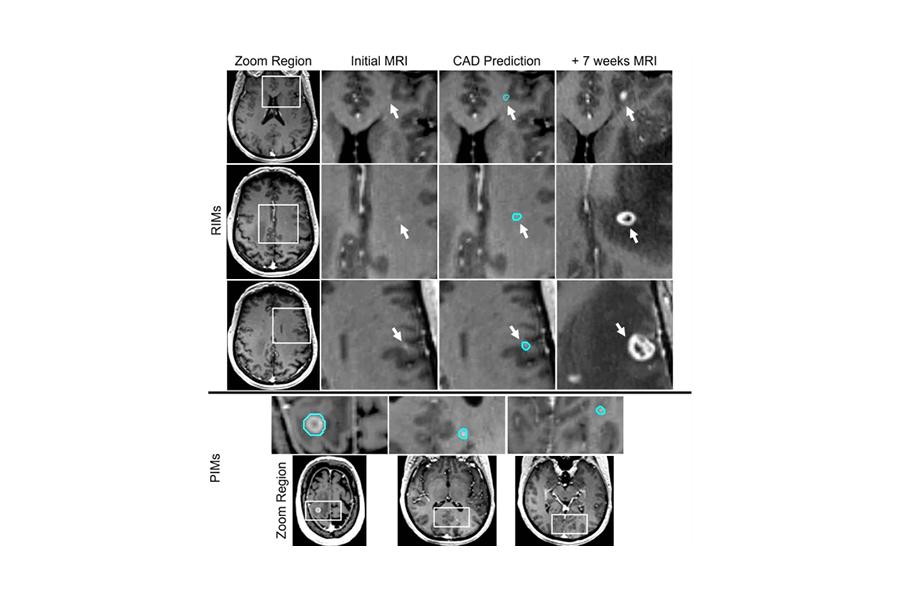

Fairchild AT, Salama JK, Wiggins WF, Ackerson BG, Fecci PE, Kirkpatrick JP, Floyd SR, Godfrey DJ. A Deep Learning-Based Computer Aided Detection (CAD) System for Difficult-to-Detect Brain Metastases. Int J Radiat Oncol Biol Phys. 2022 Oct 21;. doi: 10.1016/j.ijrobp.2022.09.068. [Epub ahead of print] PubMed PMID: 36289038.

Congratulations to our team working on computer-aided detection of brain metastases!